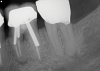

Other common risks associated with post placement include the occurrence of root fracture, perforation, and apical leakage as well as the development of caries (Figure 1 through Figure 3).9 How the post space is prepared significantly affects the ability of the root canal filling material to create a seal.11 Apical leakage increases in correlation with the amount of gutta percha removed from an endodontically treated tooth, increasing the risk of reinfection.11 The risks of fracture and perforation must also be seriously considered. After the performance of endodontic treatment alone, furcation-side dentin thickness in the distal roots of mandibular molars has been shown to be less than 1 mm in more than 80% of teeth.12 After preparation of the post space, the remaining dentin thickness in the buccal roots of premolars has been shown to be often less than 1 mm.13 The remaining thickness of the root dentin after endodontic and post placement procedures is the factor most highly correlated with future resistance against root fractures.13 These anatomic studies underscore the need for judicious preparation, and the risks of post placement underscore the need for careful case selection.

(1.) A radiograph of a root fracture associated with a threaded post, cone-beam computed tomography views of a perforation associated with a post, and a radiograph demonstrating evidence of apical leakage associated with posts, respectively.

Figure 1